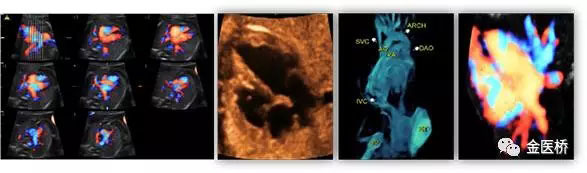

胎兒心臟超聲又名胎兒超聲心動圖,是一種無創(chuàng)、安全的影像學檢查,也是胎兒期唯一有效的能夠顯示胎兒心臟結(jié)構(gòu)、血流及評估心臟功能的影像學手段,在產(chǎn)前及時診斷,隨診,預后判斷至關(guān)重要,不可替代。